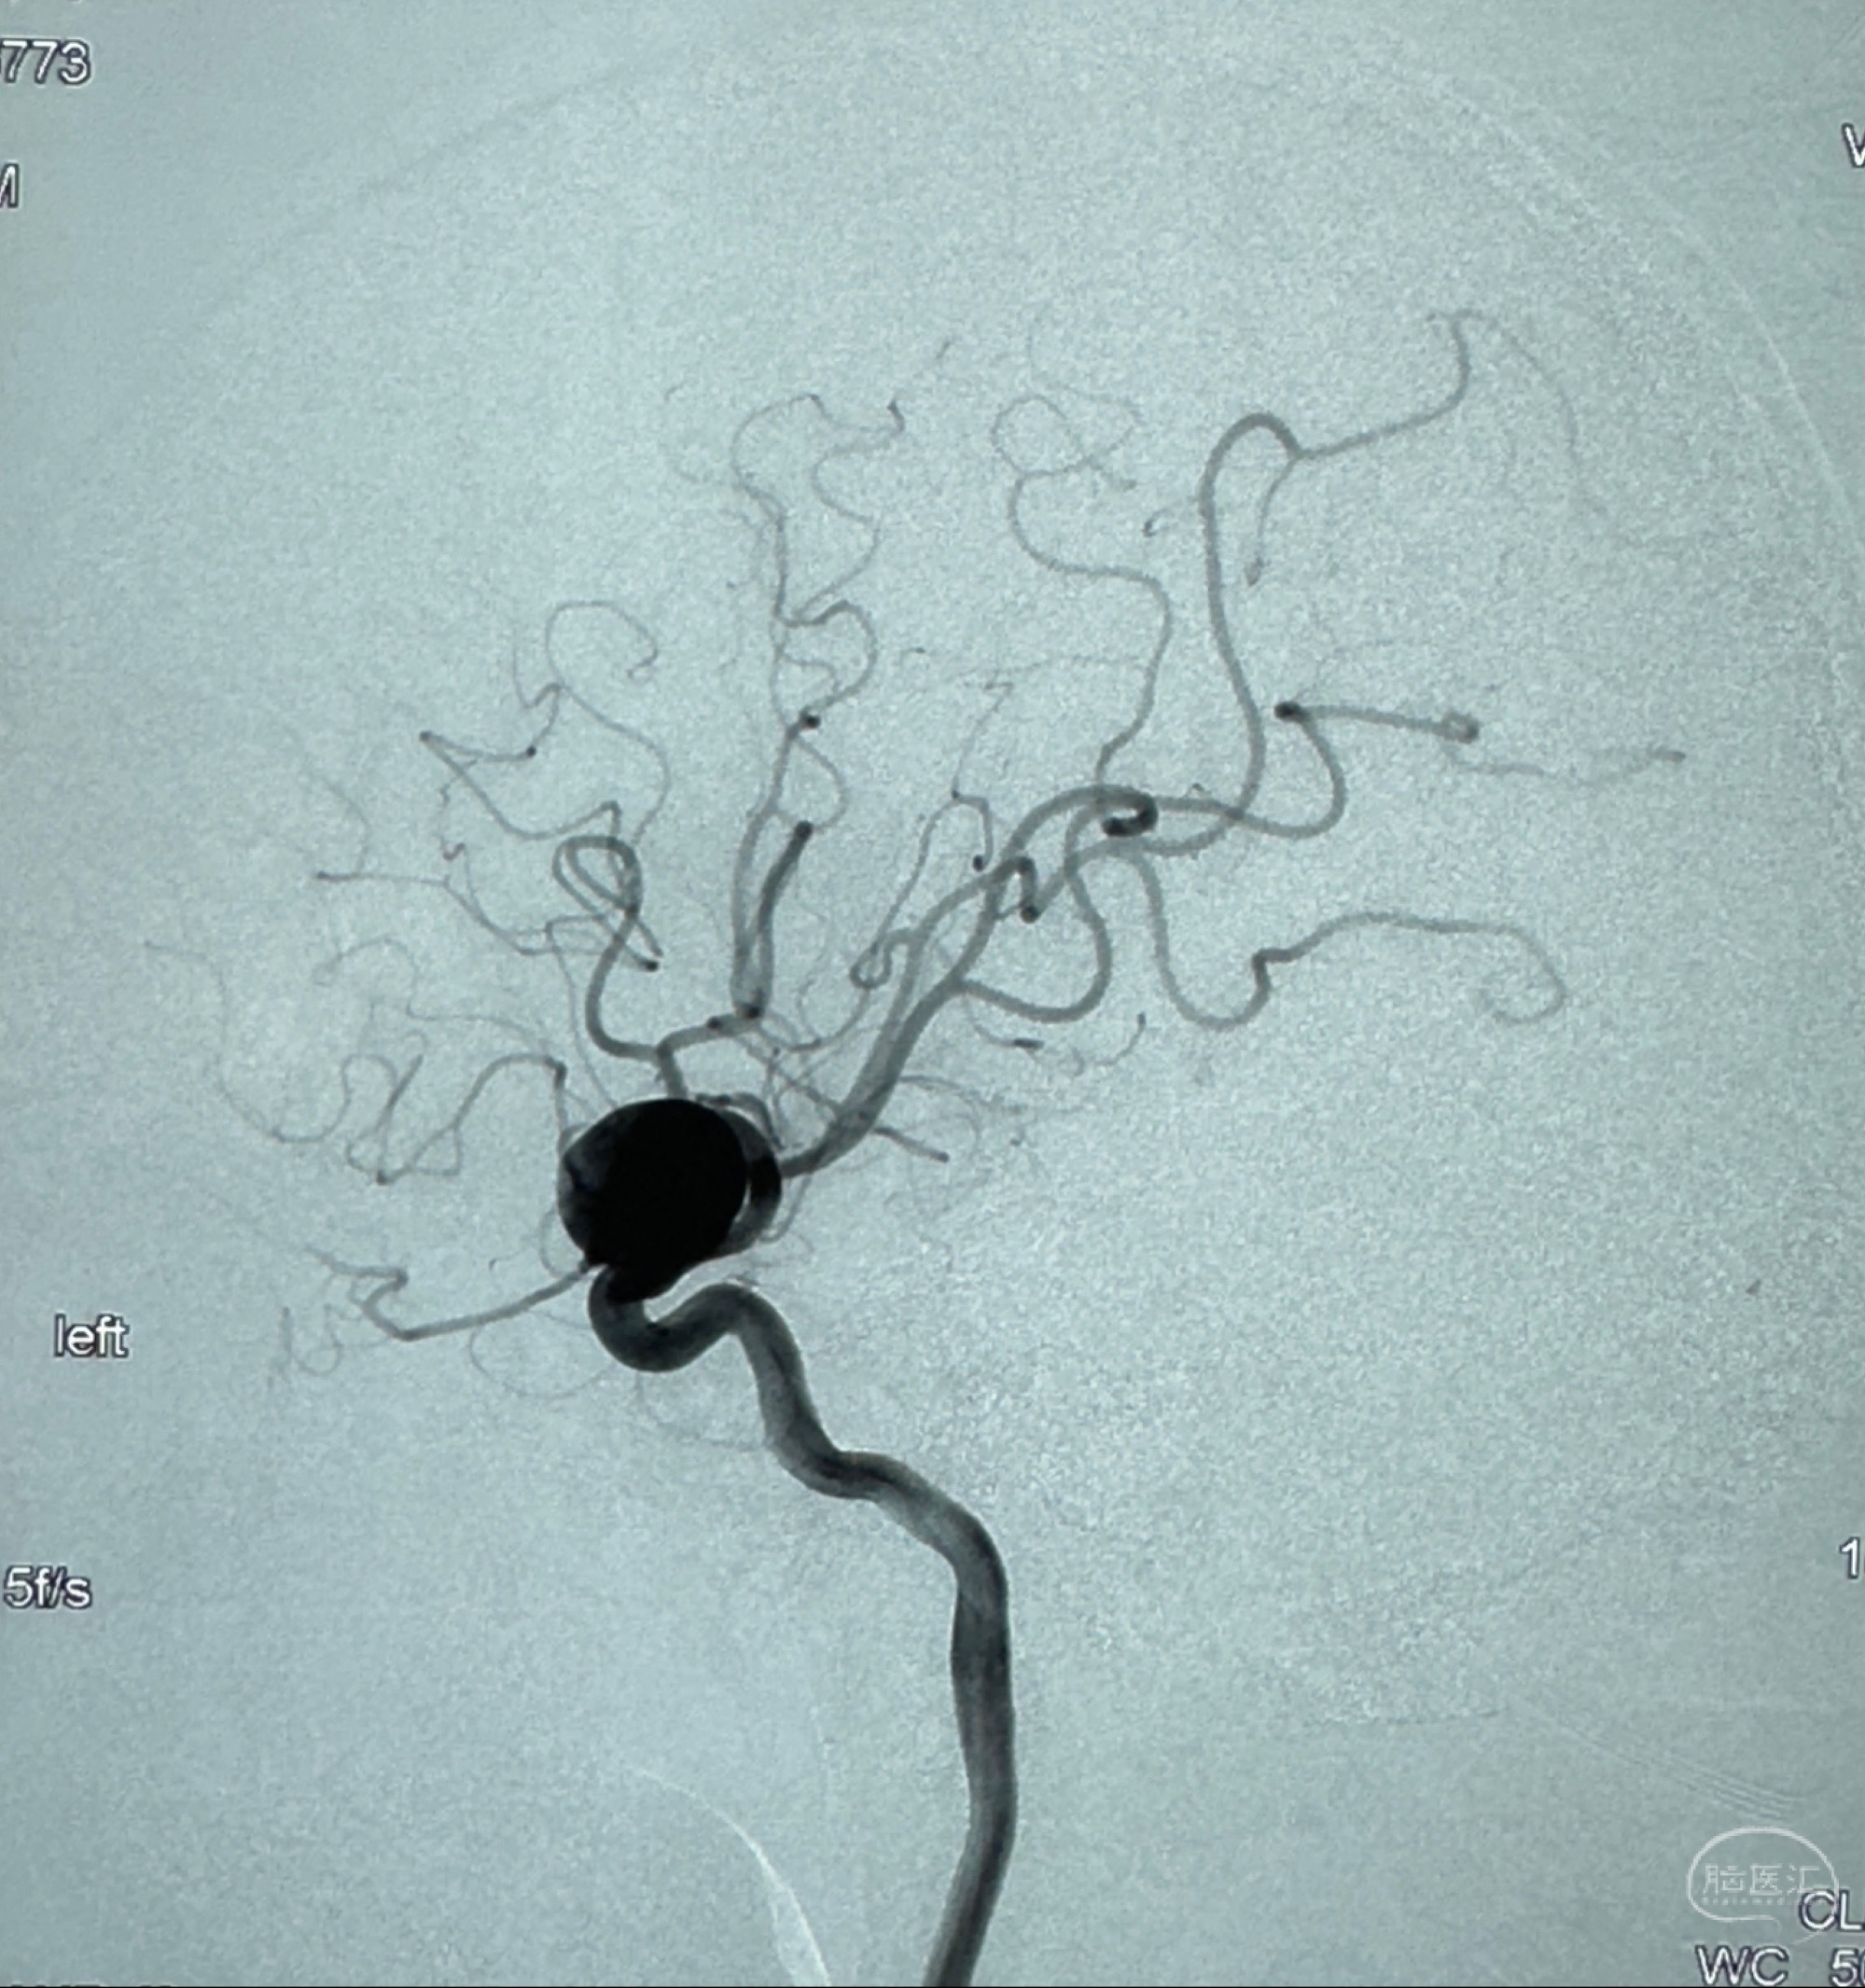

2023-12-27术后第十天复查DSA

支架贴壁佳,但可见射流,咋办?

2024-01-08全麻下再行植入密网支架一枚

Tubridge 4.5-35mm

支架植入顺利,贴壁佳,支架内血流通畅,动脉瘤内血液滞留明显